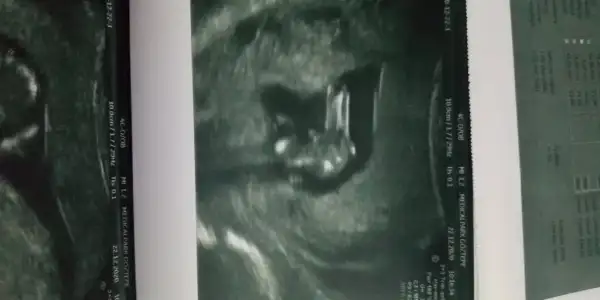

Amin canim dr guveniyorum.kizimida 12 haftalikken kesin dedi bunada net erkek dedi bak bacaklarini acmis pipi duruyor atayim resim

Eklentiler

• IMG_20201222_174055.webp

IMG_20201222_174055.webp

18,7 KB · Görüntüleme: 66